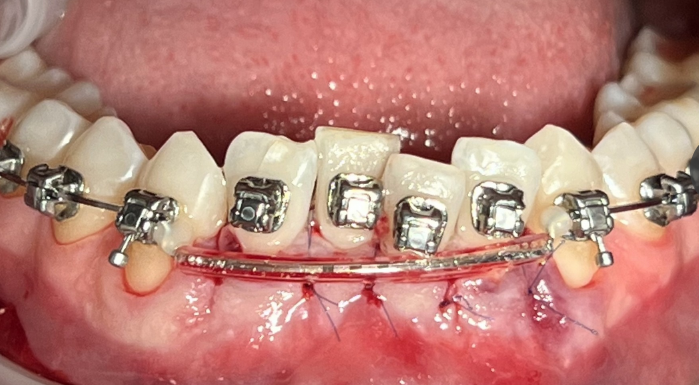

Наш опыт проведения кортикотомии

В нашей клинике операцию кортикотомии проводит хирург-пародонтолог Елена Юрьевна Вайцнер. Операция помогла сотням пациентов добиться выраженных результатов за короткий период. Один из примеров лечения пациентки.

После обследования у ортодонта было принято решение о лечении на брекетах. В январе была проведена операция, после чего началось наиболее активное перемещение зубов в заданное положение. Уже через 3 месяца (в апреле) удалось добиться столь выраженного результата без последствий и осложнений. Без операции на такое перемещение потребуется от полугода.